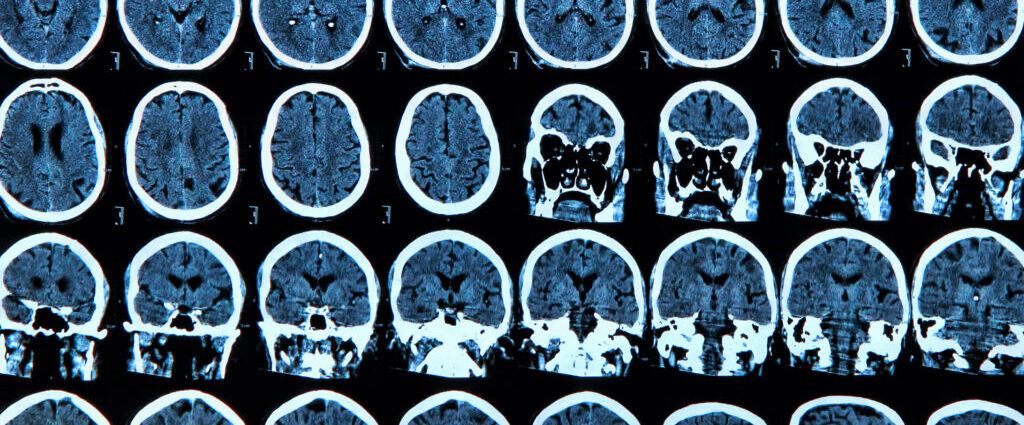

Circa 1970, the renowned Russian neuropsychologist Alexander Luria together with Karl Pribram from Stanford University and other neuroscientists of that era introduced the term “executive functions” into the scientific lexicon to denote complex behaviors such as attention and awareness. They identified the frontal lobe — the front of the brain — as the “executive of the brain” responsible for these behaviors based on their experiments with primates and patients with specific brain injuries.

Over time, the concept evolved to include mental processes needed to focus, concentrate, and pay attention when challenged by multiple simultaneous sources of information to weigh options and make informed decisions as opposed to impulsive ones.